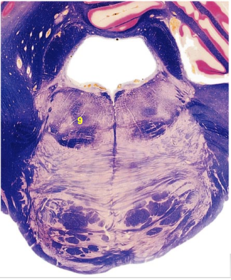

| Superior vestibular nucleus | |

| Medial lemniscus | |

| Trapezoid body | |

| Ventral trigeminothalamic tract | |

| Superior olive | |

| Longitudinal pontine fibers (corticospinal tract) | |

| Transverse pontine fibers (dark fibers) | |

| Pontine nuclei (pale) | |

| Central tegmental tract | |

| ALS | |

| Medial longitudinal fasciculus | |

| Middle cerebellar peduncle | |

| Superior cerebellar peduncle | |

| Anterior spinocerebellar tract | |

| Principle nucleus of V | |

| Mesencephalic V tract | |

| Trigeminal root fibers | |

| Motor nucleus of V | |

| Cerebellar vermis | |

| Lateral lemniscus | |

| Longitudinal pontine fibers (c-spinal, c-bulbar, c-pontine fibers) | |

| Transverse pontine fibers (dark) | |